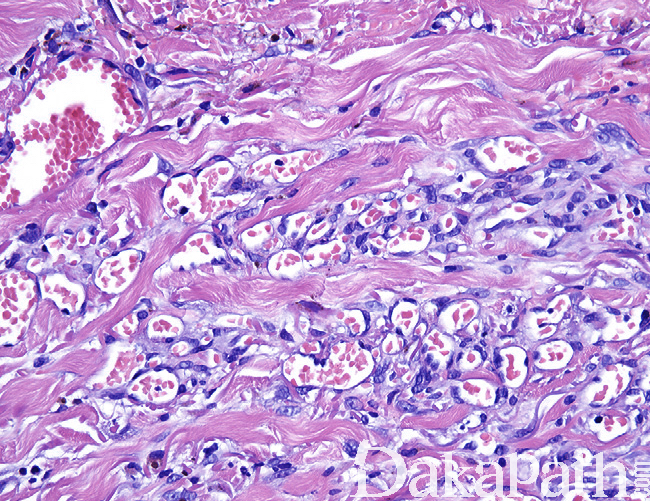

- 病变边界不清,主要累及真皮,偶见扩散入皮下组织内,由簇状增生的毛细血管组成,呈弥漫型、小叶状和弥漫-小叶混合型分布;

- 簇状增生的毛细血管排列紧密,内皮无明显的异型性,无复层内皮细胞增生表现,部分病例内皮可呈上皮样,内皮的周围均可见增生的周皮细胞;

- 少数病例中可见扩张的海绵状血管;

- 少数病例血管分割胶原纤维,但血管腔内无乳头状突起;

- 血管内常见纤维素性血栓形成,可伴机化,血管周围可见灶性的红细胞渗出;

- 大多数病例间质内可见含铁血黄素性沉着及慢性炎症细胞浸润,真皮的间质常见筋膜炎样反应性增生。